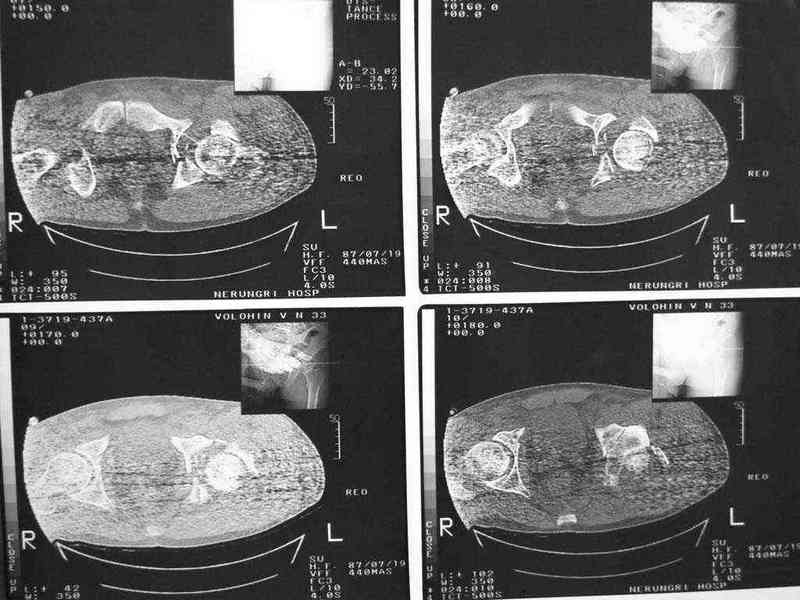

Уважаемые коллеги, нужна помощь, поступил больной с переломом лонной и седалищной кости слева, перелом вертлужной впадины слева, нестабильный вывих левой бедренной кости.

Попытки вправить бедренную кость- безуспешны. На данный момент находится на скелетном вытяжении, посоветуйте какую тактику ведения данного больного выбрать оптимально.Спасибо.